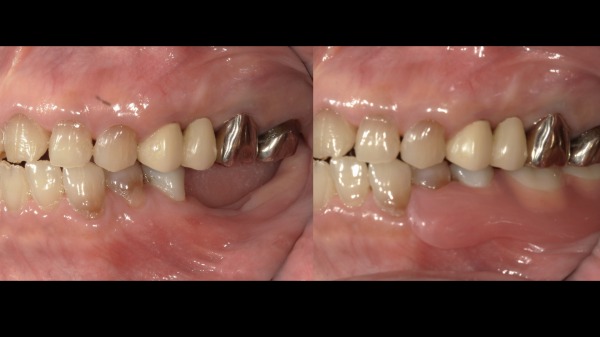

③セット

2週間ほどで入れ歯が出来上がってきました。

こちらがノンクラスプデンチャーの写真になります。

適合が問題ないことや歯茎とぶつかっている部位がないことなど念入りに確認し、噛み合わせも細かく調整を行いセットいたしました。毎日ご自身で着脱を行なってもらいますので、着脱の練習も十分にしてもらいました。